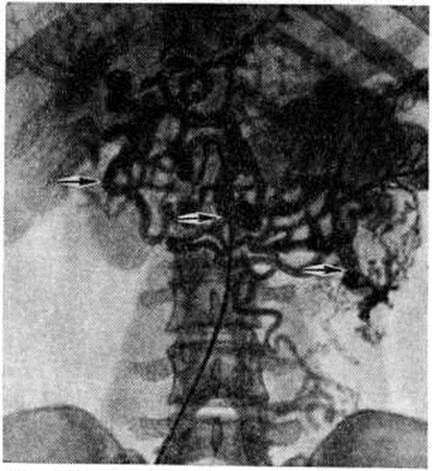

Рис. 6.

Ретроградная мезентерикопортограмма при непроходимости магистральных сосудов портальной системы: конгломерат расширенных сосудов в области ворот печени, селезёнки и желудка (указан стрелками).